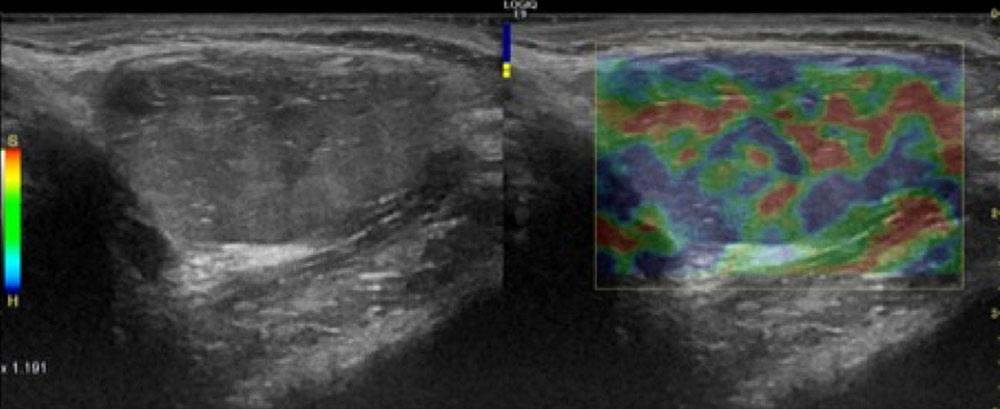

If imaging is ever necessary, sonography is the first choice. Thrombophlebitis is easily visualized within the anechoic venous malformation components as echogenic, non-compressible circumscribed foci.

On sonography, a normal vein or venous malformation is soft and readily compressible with the transducer. The non-clotted blood is virtually anechoic (black), and slow blood flow is detectable on color-coded duplex sonography.

As the blood clot matures with time, it becomes more echogenic sonographically, making it easy to distinguish from anechoic blood. Often starting at the edge, i.e., at the vessel wall, there is a slow recanalization of the involved vessel. This is visible as anechoic fluid around the echogenic thrombus.

In ultrasound elastography, thrombi tend to be harder than the surrounding tissue. Therefore they are also relatively easy to detect according to the color scaling setting.